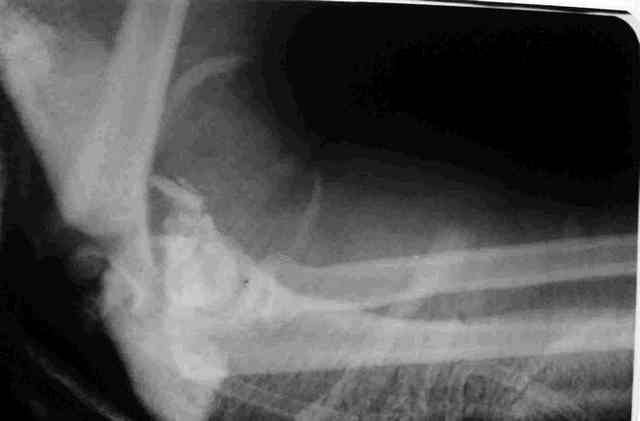

Прошу оказать помощь в определении дальнейшей тактики лечения открытого оскольчатого перелома дистального отдела плеча, осложненного гнойной инфекцией у пациентки с сочетанной травмой. Пациентка получила сочетанную травму в результате падения с высоты.В числе прочих повреждений открытый оскольчатый перелом дистального отдела плечевой кости.Выполнено ПХО, гипсовая иммобилизация.На следующие сутки клиника гнойной инфекции.Произведена вторичная гнойная хирургическая обработка раны, стабилизация перелома аппаратом, вакуумное дренирование.В настоящий момент гнойного отделяемого нет. (отделяется синовиальная жидкость. Наложены вторичные швы.Вопрос - какова дальнейшая тактика в случае заживления раны ( открытый остеосинтез или функциональное лечение).Что делать в случает возобновления гнойного процесса.